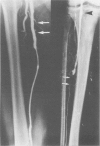

Images in this article